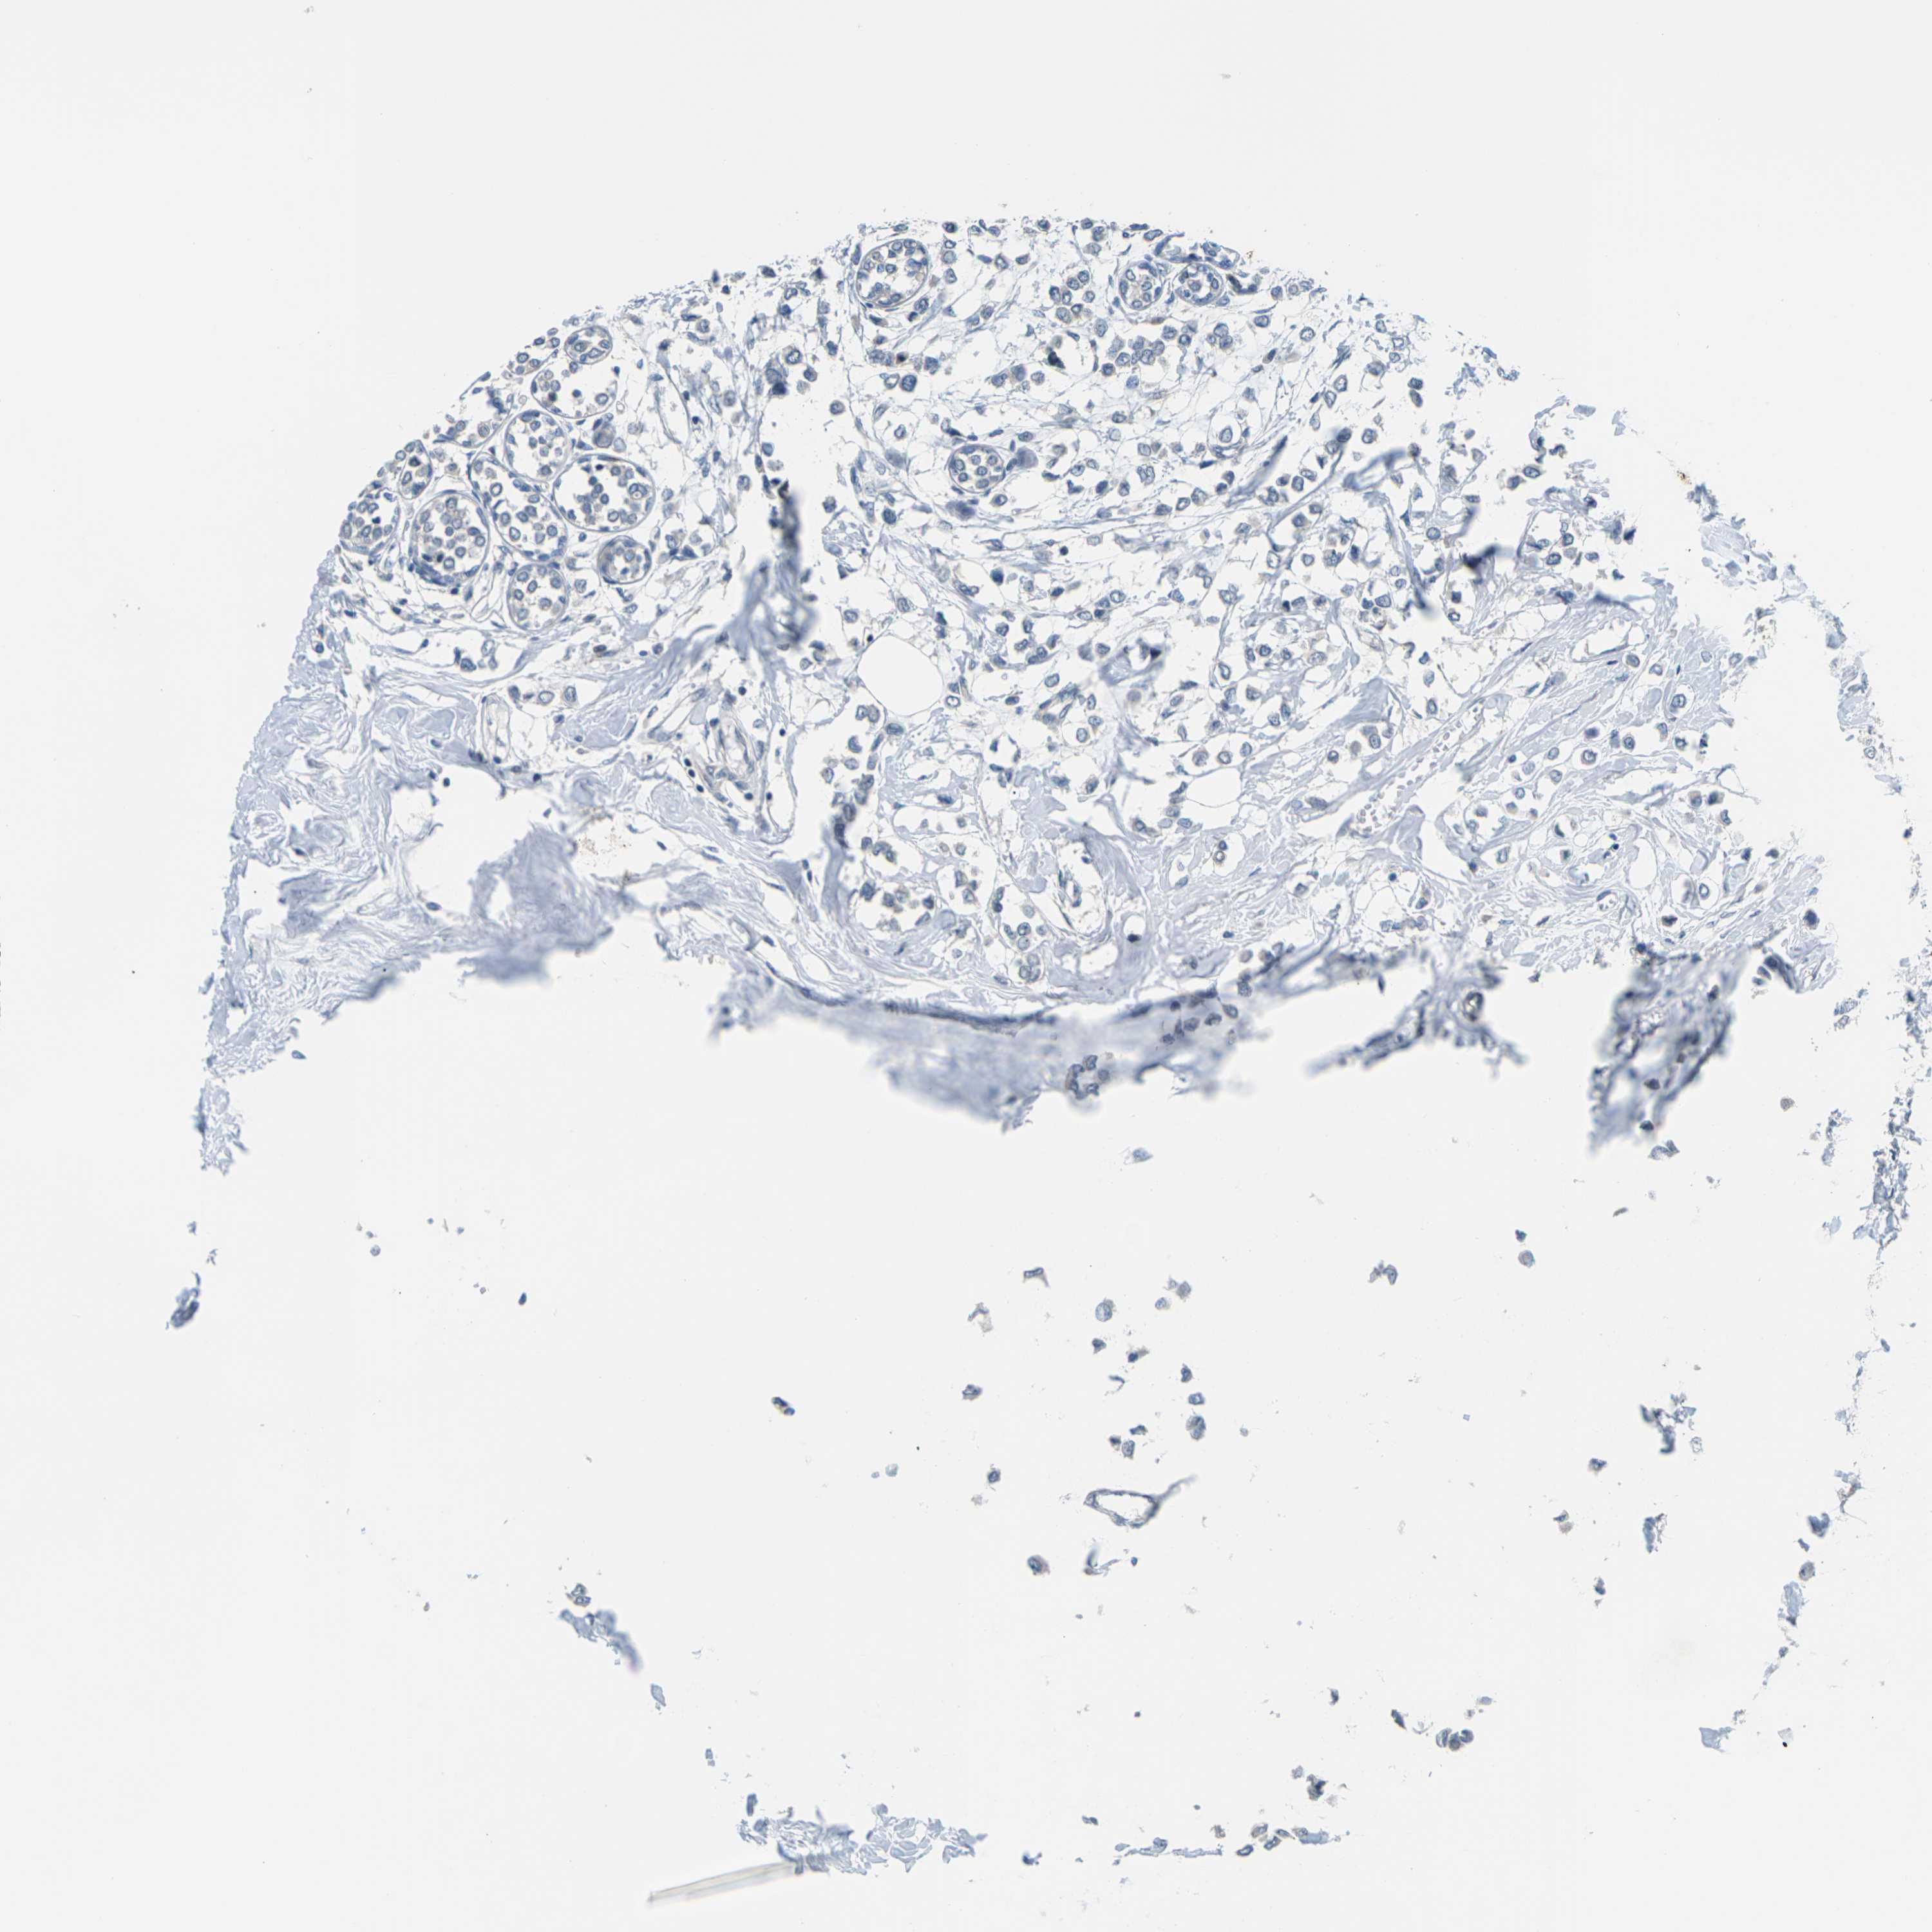

BRCA TCGA BRCA VALIDATION PROTEIN EXPRESSION